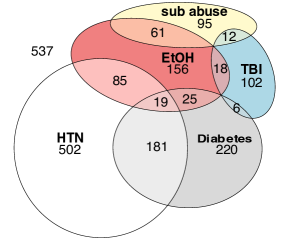

Age prediction using brain imaging, such as MRIs, has achieved promising results, with several studies identifying the model’s residual as a potential biomarker for chronic disease states. In this study, we developed a brain age predictive model using a dataset of 1,220 U.S. veterans (18–80 years) and convolutional neural networks (CNNs) trained on two-dimensional slices of axial T2 weighted fast spin-echo and T2 weighted fluid attenuated inversion recovery MRI images. The model, incorporating a degree-3 polynomial ensemble, achieved an of 0.816 on the testing set. Images were acquired at the level of the anterior commissure and the frontal horns of the lateral ventricles. Residual analysis was performed to assess its potential as a biomarker for five ICD-coded conditions: hypertension (HTN), diabetes mellitus (DM), mild traumatic brain injury (mTBI), illicit substance abuse/dependence (SAD), and alcohol abuse/dependence (AAD). Residuals grouped by the number of ICD-coded conditions demonstrated different trends that were statistically significant (), suggesting a relationship between disease states and predicted brain age. This association was particularly pronounced in patients over 49 years, where negative residuals (indicating advanced brain aging) correlated with the presence of multiple ICD codes. These findings support the potential of residuals as biomarkers for detecting latent health conditions.

The target BARB for this model focused on 5 challenging conditions: alcohol

abuse/dependence (AAD), substance abuse (SAD), hypertension (HTN), diabetes mellitus (DM), and mild traumatic brain injury (mTBI). These conditions are often underreported, inconsistently managed, or clinically subtle. Hence these conditions would benefit from a BADB. Despite the promise of this approach, the results demonstrated only modest correlations between brain age residuals and these conditions. We surmise this is likely due to the statistical hurdles discussed earlier as well as challenges in labeling. For example, the binary labeling of these 5 ICD codes can lack the subtly of distinguishing between well-managed and poorly managed disease states. In the case of AAD and SAD, it seems possible and likely that several samples are mislabeled as lacking one or both disorders.

Additionally, the dataset includes five binary ICD codes for disease states, where 1 corresponds to a diagnosis within the patient’s chart. The five conditions tracked are hypertension (HTN), diabetes mellitus (DM), mild traumatic brain injury (mTBI), illicit substance abuse/dependence (SAD), and alcohol abuse/dependence (AAD), which are observed as influencing brain structures [18, 33, 35, 36] except for mTBI, which has been show to be visible only after several injuries in animal models [11]. Each of these codes presents unique challenges. In the case of mTBI, SAD, and AAD are commonly hidden conditions that rely on patient disclosure. Both HTN and DM, extremely common in the population, exhibit wide variability in severity and management. So it is possible that a patient with an HTN diagnosis may be asymptomatic if the condition is well-managed, thereby having a positive residual (indicating a “younger” brain) while another patient may qualify as AAD but fail to disclose this information yet correspond to a negative residual (indicating an “older” brain). With this dataset, we have no way of determining this lurking factor.

Recall, however, the dataset’s lack of distinction for “healthy” brains: this will introduce a baseline error. Even if the model is well constructed and the residuals lack an outsized influence of model bias and/or variance, the baseline may not correspond to right target state, depending on the data, making it more challenging to detect disease states. It is therefore not surprising that no significant associations were found for DM, mTBI, or AAD in mean residuals. An ANOVA test did reveal significant differences in mean residuals for HTN and SAD (). Notably, HTN displayed an inverse correlation with the brain age residual, indicating younger predicted brain ages relative to chronological age (). This inverse relationship may reflect variability in the neurological effects of HTN based on factors such as disease management and severity, which the dataset does not differentiate. When assessing the positive correlation between SAD and brain age residuals, it is possible that patients with more severe cases are more likely to volunteer this information but this is only speculation.

A key limitation of the dataset is the binary nature of the ICD codes, which indicates only the presence or absence of a condition without additional details. For example, DM is not supplemented with A1C levels, and HTN lacks systolic or diastolic measurements. We have no way of assessing if individuals with well-managed conditions may exhibit different neurological effects compared to those with poorly managed conditions, because both are assigned the same ICD code. Further complicating the interpretation of results is the reliance on self-reported information for mTBI, SAD, and AAD. This reliance introduces the possibility of underreporting, as individuals meeting the criteria for these conditions may not disclose them. Recording inconsistencies may also exist, with some patients meeting ICD code criteria inaccurately labeled in the dataset. These factors, especially combined with the baseline issue, collectively complicate the understanding of this model residual’s correlation with specific disease states.

Although the dataset lacks granularity and may be inconsistent with labels of these five disease states, which confounds direct prediction of the specific ICD codes and produces conflicting results with ANOVA tests, we can still assess if there is a correspondence with the model residual and the disease states. Since labeling inconsistencies and misclassification are assumed to occur randomly across the dataset, any systematic relationship between negative residuals—-where the predicted brain age exceeds the chronological age—-and the presence of ICD codes would provide evidence of a meaningful correlation. Figure 7 captures exactly this. When organizing subjects in the training set by how many ICD codes are associated to them, we see each group’s trend line to be distinct (). This means that given an actual age and the number of ICD codes, the predicted age will change. In particular, those with two or more trend toward an older brain age.

The residual analysis did not find compelling associations between the model errors and any one of the five ICD codes considered: substance abuse/dependence (SAD), alcohol abuse/dependence (AAD), mild traumatic brain injury (mTBI), diabetes mellitus (DM) and hypertension (HTN). This may have been due to labeling issues. In aggregate, the labels had a compelling association with negative residuals (an older predicted brain age), which became definitive when we considered If the patient was older than 49. These findings provide evidence that the residuals, or the difference between predicted and actual brain age, may serve as potential brain age residual biomarkers (BARBs) for identifying subtle or latent health conditions.